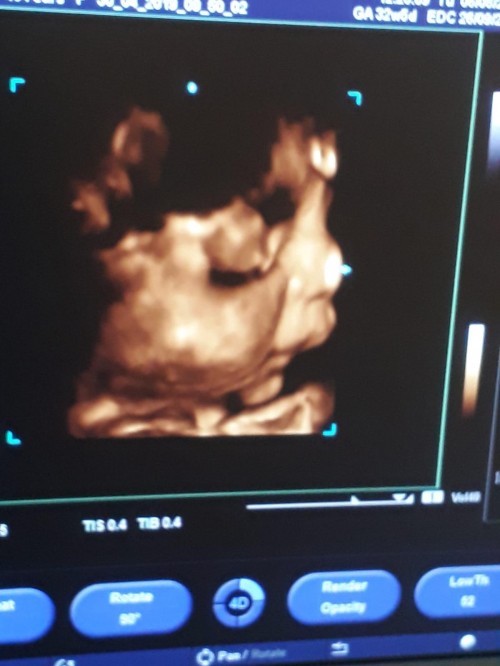

ağzını yüzünü yediğim zorda olsa gösterdi kendini azcik:)

Allah razi olsun canim cok nazli olacak zor gördük: )

Eyvah eyvah annesi cekicegin var o zmn oglusundan:)

aynen canim hayirlisiyla alalim kucağımizada teyzesi 4 yildir yolunu gozluyorduk:)

Yanaklara bak yuvarlak yuvarlakkk :))

evet canim Topak burunlu bide esime diyom bak sana benziyor bi seviniyor: ))

:))) rabbim sag salim kucaginiza aldirsin ins :)

amin canim Allah razi olsun:)

kiizz bnunn agzii burnuu pıtttttt yaaaaaaa ❣❣❣:D ne kibarr agizlii burunluu allahimm allahimm masaallh nazardan korusun rabbim

teşekkür ederiz teyzesi Allah razi olsun:)